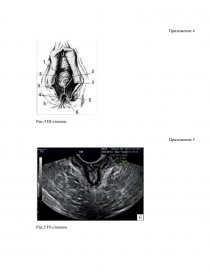

Проблема родового травматизма у женщин, перенесших роды через естественные родовые пути, является важной проблемой современного акушерства. Повреждение во время родов, особенно первородящих, – довольно частое осложнение.Травматизация мягких тканей родового канала наблюдается у каждой 3 - 5-й роженицы. Разрыв промежности – это разрыв кожи и других структур мягких тканей, которые у женщин отделяют влагалище от заднего прохода. Разрыв промежности в основном возникает у женщин в результате вагинальных родов, которые напрягают промежность. Это наиболее распространенная форма акушерской травмы. Разрыв промежности отличается от эпизиотомии, при которой промежность намеренно разрезается, чтобы облегчить доставку. Согласно литературным данным травмы родовых путей (разрывы шейки матки, стенок влагалища, промежности и вульвы) составляют до 40 % случаев, у первородящих они встречаются в 73 % случаев, а при акушерских операциях (наложение акушерских щипцов, вакуум-экстратора и др.) достигают 90 %. Разрывы промежности III степени колеблются от 0,4 до 5 %.

Акушерские травмы промежности наблюдаются достаточно часто и обусловлены множеством причин. Предрасполагают к разрыву промежности половой инфантилизм, высокая промежность, рубцовые изменения тазового дна после предшествующих травм в родах или пластических операций. Наступлению разрыва промежности так же могут способствовать крупные размеры головки, неправильное ее вставление, наличие предшествующих разрывов промежности.